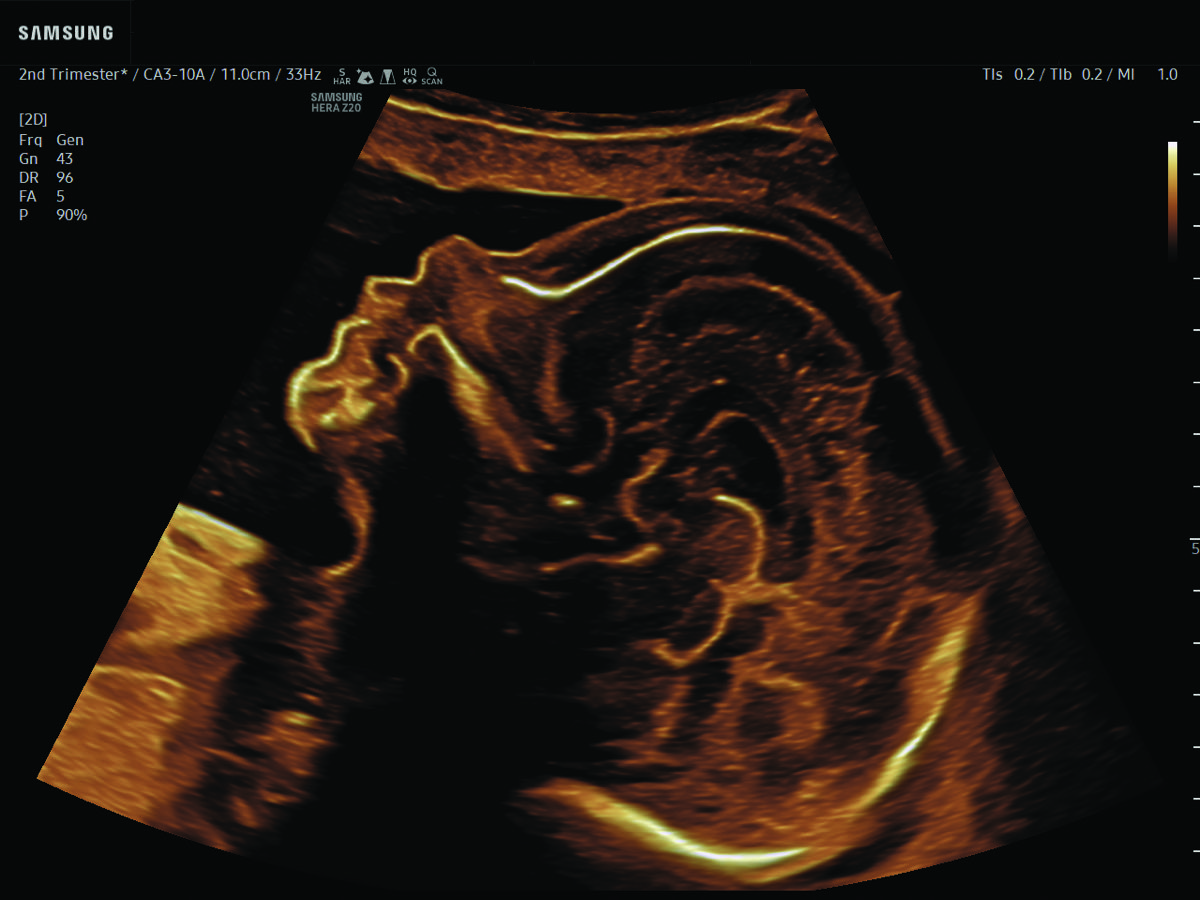

Comprehensive, advanced and expert MFM care for high-risk pregnancies

- Fetal anomalies